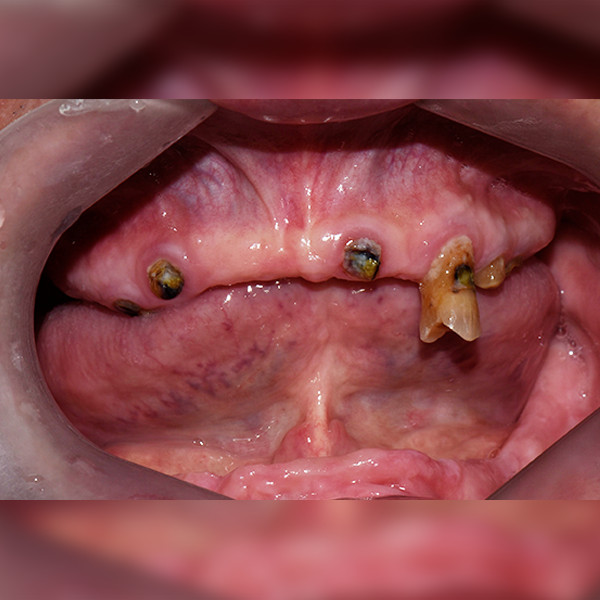

3. Trường hợp 56 Ông/Bà Jeong*ju, 70 tuổi 2018-04-05 / 2018-11-08

Trường hợp 56 Ông/Bà Jeong*ju, 70 tuổi 2018-04-05 / 2018-11-08

Before Before

After After